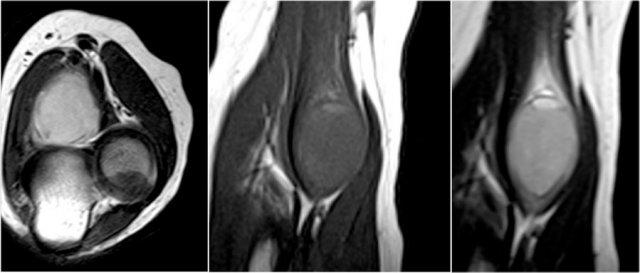

Đây là các hình ảnh mặt phẳng đứng dọc và mặt phẳng ngang của một bệnh nhân được chuyển đến bác sĩ phẫu thuật ung thư chỉnh hình vì một khối u gần khuỷu tay.

Có một vết rách một phần (mũi tên) của gân cơ nhị đầu, nhưng câu hỏi đặt ra là, cấu trúc mà chúng ta đang quan sát là gì và bên trong nó chứa gì.

Cấu trúc này là túi hoạt dịch quay-nhị đầu, vì vậy đây là viêm túi hoạt dịch.

Cần nhớ rằng gân cơ nhị đầu không có bao gân, do đó viêm bao gân không phải là khả năng có thể xảy ra.

Chẩn đoán phân biệt cho các cấu trúc cường độ thấp trong túi hoạt dịch bao gồm: chondromatosis màng hoạt dịch, viêm màng hoạt dịch thể sắc tố dạng nốt (PVNS) và thể hạt gạo.

Hóa ra đây là các thể gạo (rice bodies).

Trong bất kỳ khớp hoặc túi thanh dịch nào có lớp màng hoạt dịch, các thể gạo này có thể được hình thành do viêm mạn tính kèm theo tăng sản màng hoạt dịch.

Các nhung mao sẽ phát triển vượt quá nguồn cung cấp máu của chúng, trở nên hoại tử và rơi vào trong khớp hoặc túi thanh dịch.

Chúng được gọi là thể gạo vì khi mở khớp ra, chúng trông giống như những hạt gạo.

Here another case.

Mũi tên trắng trong hình bên trái đang chỉ vào túi hoạt dịch.

Lưu ý rằng cơ nhị đầu vẫn còn nguyên vẹn.

Bên cạnh túi hoạt dịch quay-nhị đầu (mũi tên vàng), một túi hoạt dịch gian cốt (mũi tên đỏ) cũng đã được Abdalla Skaf mô tả trên tạp chí Radiology trong bài báo có tiêu đề: Viêm túi hoạt dịch nhị đầu-quay: Các dấu hiệu trên hình ảnh MRI.

Đôi khi các khối này có thể giống u bướu hoặc có thể gây chèn ép dây thần kinh quay khi chúng trở nên rất lớn.